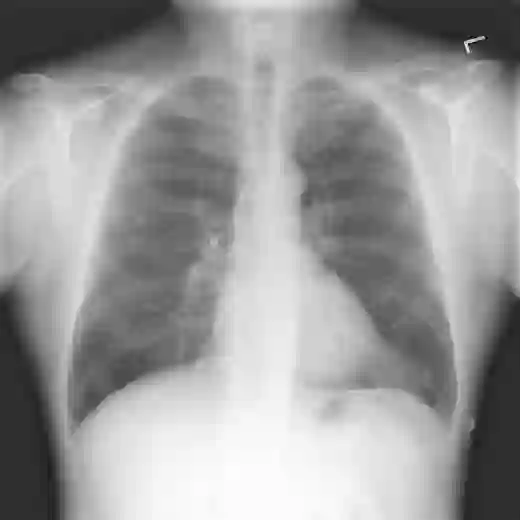

The remarkable success of deep learning has prompted interest in its application to medical imaging diagnosis. Even though state-of-the-art deep learning models have achieved human-level accuracy on the classification of different types of medical data, these models are hardly adopted in clinical workflows, mainly due to their lack of interpretability. The black-box-ness of deep learning models has raised the need for devising strategies to explain the decision process of these models, leading to the creation of the topic of eXplainable Artificial Intelligence (XAI). In this context, we provide a thorough survey of XAI applied to medical imaging diagnosis, including visual, textual, example-based and concept-based explanation methods. Moreover, this work reviews the existing medical imaging datasets and the existing metrics for evaluating the quality of the explanations. In addition, we include a performance comparison among a set of report generation-based methods. Finally, the major challenges in applying XAI to medical imaging and the future research directions on the topic are also discussed.